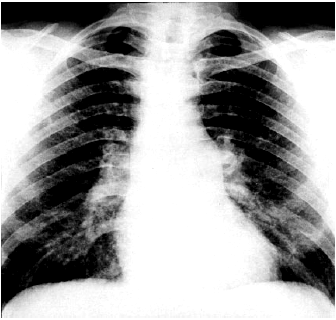

Рентгенологическое исследование позволяет уточнить характер поражения легких, а также выявить несколько важных рентгенологических признаков, указывающих на увеличение размеров ПЖ и наличие легочной АГ (рис. 13.12 и 13.13):

1. Выбухание ствола легочной артерии в правой передней косой проекции и реже в прямой проекции (расширение II дуги левого контура сердца).

2. Расширение корней легких.

3. Увеличение размеров ПЖ в правой и левой передней, а также в левой боковой проекциях и уменьшение ретростернального пространства (рис. 13.13).

4. Значительное выбухание заднего контура тени сердца вплоть до сужения ретрокардиального пространства, что наблюдается при выраженной гипертрофии и дилатации ПЖ, который смещает ЛЖ кзади (см. рис. 13.13, б).

5. Расширение ствола и центральных ветвей легочной артерии, которое сочетается с обеднением сосудистого рисунка на периферии легочных полей за счет сужения мелких легочных артерий.

| Рис. 13.12. Рентгенограмма сердца в прямой проекции больного с хроническим легочным сердцем |